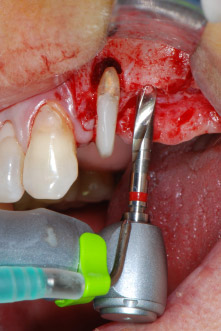

Le sedi di impianto sono state preparate in corrispondenza dei siti 25 e 26 con strumentazione rotante, utilizzando un manipolo contrangolo con una velocità di trasmissione 20:1 con motore potente di nuova generazione (Implantmed di W&H) (Fig. 8).

La preparazione finale vicino al seno mascellare è stata ancora una volta eseguita con uno strumento piezoelettrico (Piezomed, attacco S2).

La sede dell'impianto è stata preparata con un nuovo motore per impianto (Fig. 20), in combinazione con un manipolo contrangolo progettato specificamente per chirurgia e implantologia odontoiatrica.

La velocità di trasmissione 20:1 e l'elevata coppia del motore dell'impianto, fino a 6,2 Ncm, hanno permesso una preparazione, un inserimento dell'impianto e una maschiatura a bassa velocità. La preparazione finale fino alla membrana del seno mascellare è stata ancora una volta eseguita con l'unità piezoelettrica e uno strumento diamantato arrotondato.